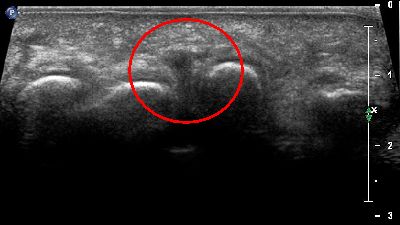

Neuroma di Hauser con ripresa longitudinale Neuroma Hauser ripresa longitudinale